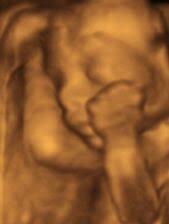

25 hafta gebelik bebek kilosu

25 haftalik gebelik